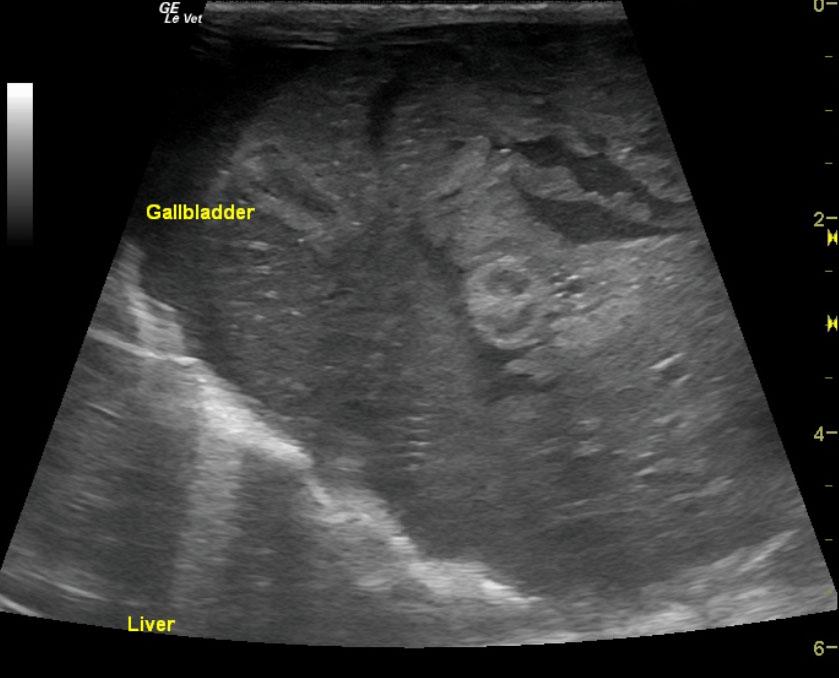

The liver was mildly heterogenous with increased portal markings and coarse architecture. The portal vein was dilated with echogenic debris. However, no evidence for portal hypertension was noted. The portal vein velocity was normal at 25 cm/sec. The echogenic debris within the portal vein was also repeated in the vena cava. This is suggestive for inspissation and a high predisposition for clot formation. The common bile duct measured 0.3 cm. The gallbladder was collapsed and double layered with debris.